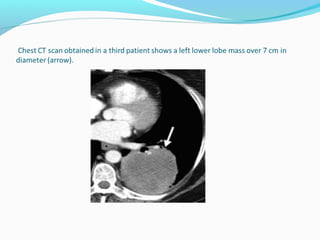

T3 - tumor

Tumor with atelectasis or obstructive pneumonitis of the

entire lung

Tumor in the main bronchus within 2 cm of the carina but

not invading it

Tumor of any size with invasion of non-vital structures

such as the chest wall, mediastinal pleura, diaphragm,

pericardium.

Separate tumour nodules in the same lobe as the primary

tumor.

T3 - tumor Tumorwith atelectasis or obstructive pneumonitis of the entire lung Tumor in the main bronchus within 2 cm of the carina but not invading it Tumor of any size with invasion of non-vital structures such as the chest wall, mediastinal pleura, diaphragm, pericardium. Separate tumour nodules in the same lobe as the primary tumor.